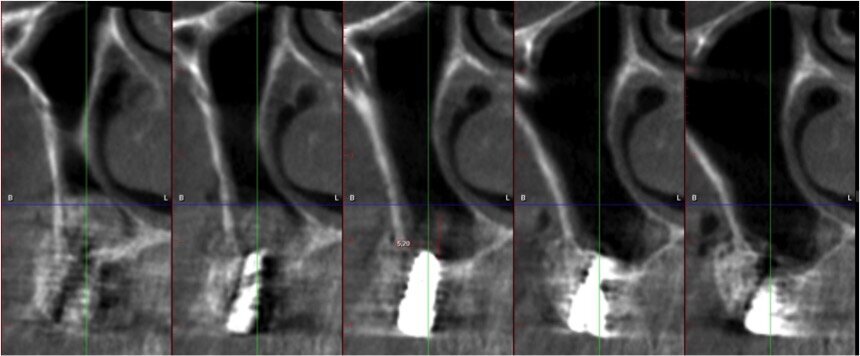

La paziente, di sesso femminile e con anamnesi medica negativa, si presenta in visita lamentando mobilità della protesi fissa presente nel II quadrante. Dopo l’esame obiettivo e strumentale gli elementi 23 e 27 (pilastri di ponte) vengono reputati non mantenibili e si programma l’estrazione degli stessi. Contestualmente all’estrazione si pianifica, con lo studio della CTCB pre-operatoria, l’inserimento di 3 impianti e la futura riabilitazione implanto-protesica fissa con pilastri di ponte 23-24-25. L’altezza di cresta residua è circa di 4/5 mm in altezza per le tre sedi (Figg. 1-4). La paziente riceve una profilassi antibiotica di tipo Short-term (Amoxicillina + Acido Clavulanico 2 g 1 ora prima dell’intervento) e fa uno sciacquo di 1 minuto con CHX 0,2% prima della chirurgia.

Fig. 2 - Cross section di zona 23.

Fig. 3- Cross section di zona 24.

Fig. 4 - Cross section di zona 25.